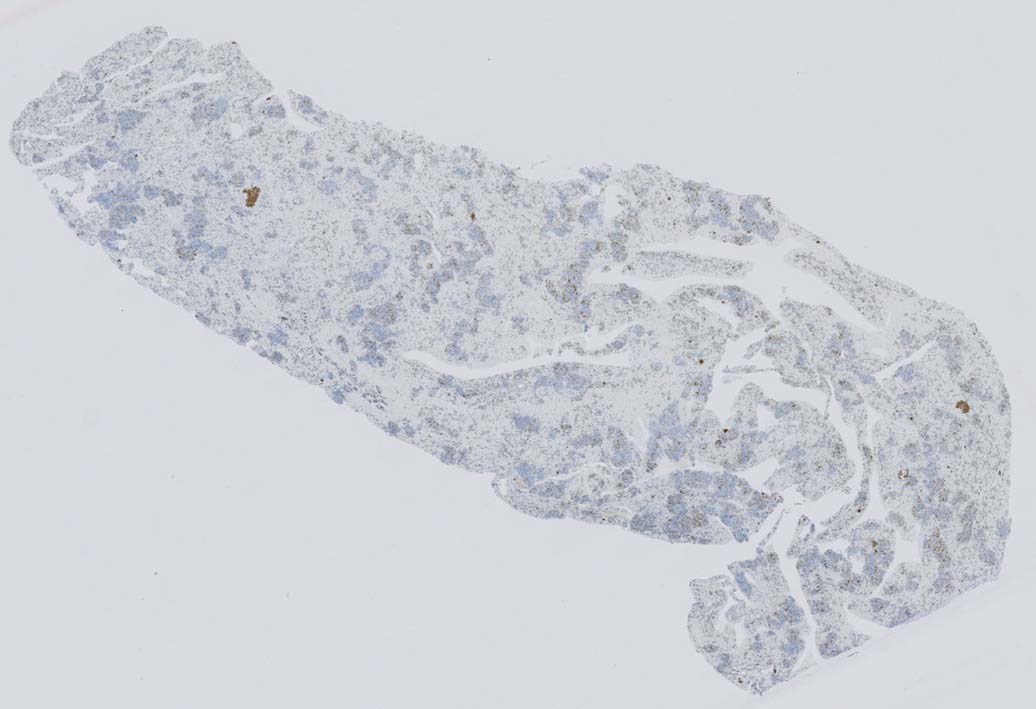

骨髄浸潤所見

同じ患者さんの骨髄所見です. (サムネイルのクリックで大きな画像が見られます.)

骨髄への腫瘍細胞浸潤はintertrabecular patternで, 腫瘍細胞は小集簇巣を形成して散在性に認められた. HE, ASD-Giemsaのみでの浸潤, 増殖の確定はなかなか難しいようです.

骨髄クロットでは, 十分量が採取されているにもかかわらず, CD3陽性細胞は微小な集簇巣が2個ほど認められるのみであとは散在している.